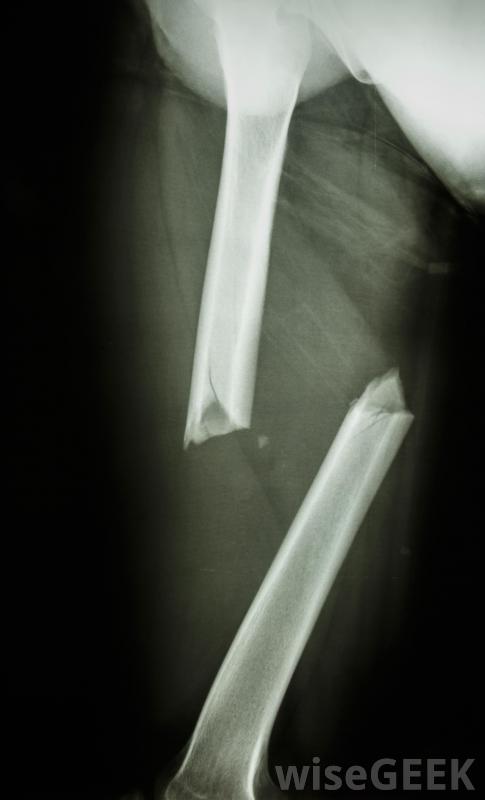

骨整合是指植入材料與活骨結合,將植入物牢固地固定在原位的現象,這種現象最早出現在20世紀初,醫生們很快就意識到了骨整合的含義,只有某些材料才能進行骨整合,鈦是以骨整合為目標的手術中最受歡迎的選擇之一。使用其他材料,組織將無法生長到植入物內部和周圍,骨整合有很大的潛力來幫助手臂和腿等假肢的人在這個過程中,骨科醫生會在手術過程中仔細地將植入物植入骨內,考慮到患者的需要,并復查x光片以確定植入物的大小和位置。在幾個月的時間里,骨開始生長到植入物中,錨定植入物就位。一旦植入物安裝好,骨頭開始長入其中,就不可能在不損壞骨骼的情況下移除,它將能夠承受重量。用于修復嚴重骨折的桿可以是骨整合的骨整合的一個明顯的用途是安裝牙科植入物這種植入物可以與頜骨結合在一起,使牙醫能夠在植入物上安裝一顆牙齒。美容牙科學和重建牙科學都可以利用這種植入技術。這個過程也可以用來為假肢、鼻子等假肢制造錨固件,和耳朵。假肢可以用骨整合錨栓更加穩定和安全地連接,提高患者的舒適性和功能性。骨整合是使牙科植入物像天然牙齒一樣工作的關鍵對于手臂和腿這樣的假肢,骨整合有著巨大的潛力。固定假肢最大的問題之一是找到一種技術,可以將植入物牢固地固定在身體上,而不會造成疼痛或限制行動自由。不恰當的附著也會使假肢基本上失去作用,因為它無法承受重量。骨整合假肢,這些問題是可以解決的。植入物通常需要六個月的時間才能成功固定在骨頭上,在這一點上,可以開始安裝假肢。用于修復嚴重骨折的桿可以進行骨整合用于修復嚴重骨折的桿也可以進行骨整合在這些過程中,桿在骨愈合的同時使其保持穩定,同時還增加了支撐和結構,以保護骨骼在將來不會再次斷裂。通過對該部位進行x光和醫學影像學研究,可以判斷骨愈合的進展,以確認骨在植入物中生長,并且骨生長均勻骨整合是指植入材料(如牙科植入物)與活骨結合的過程。